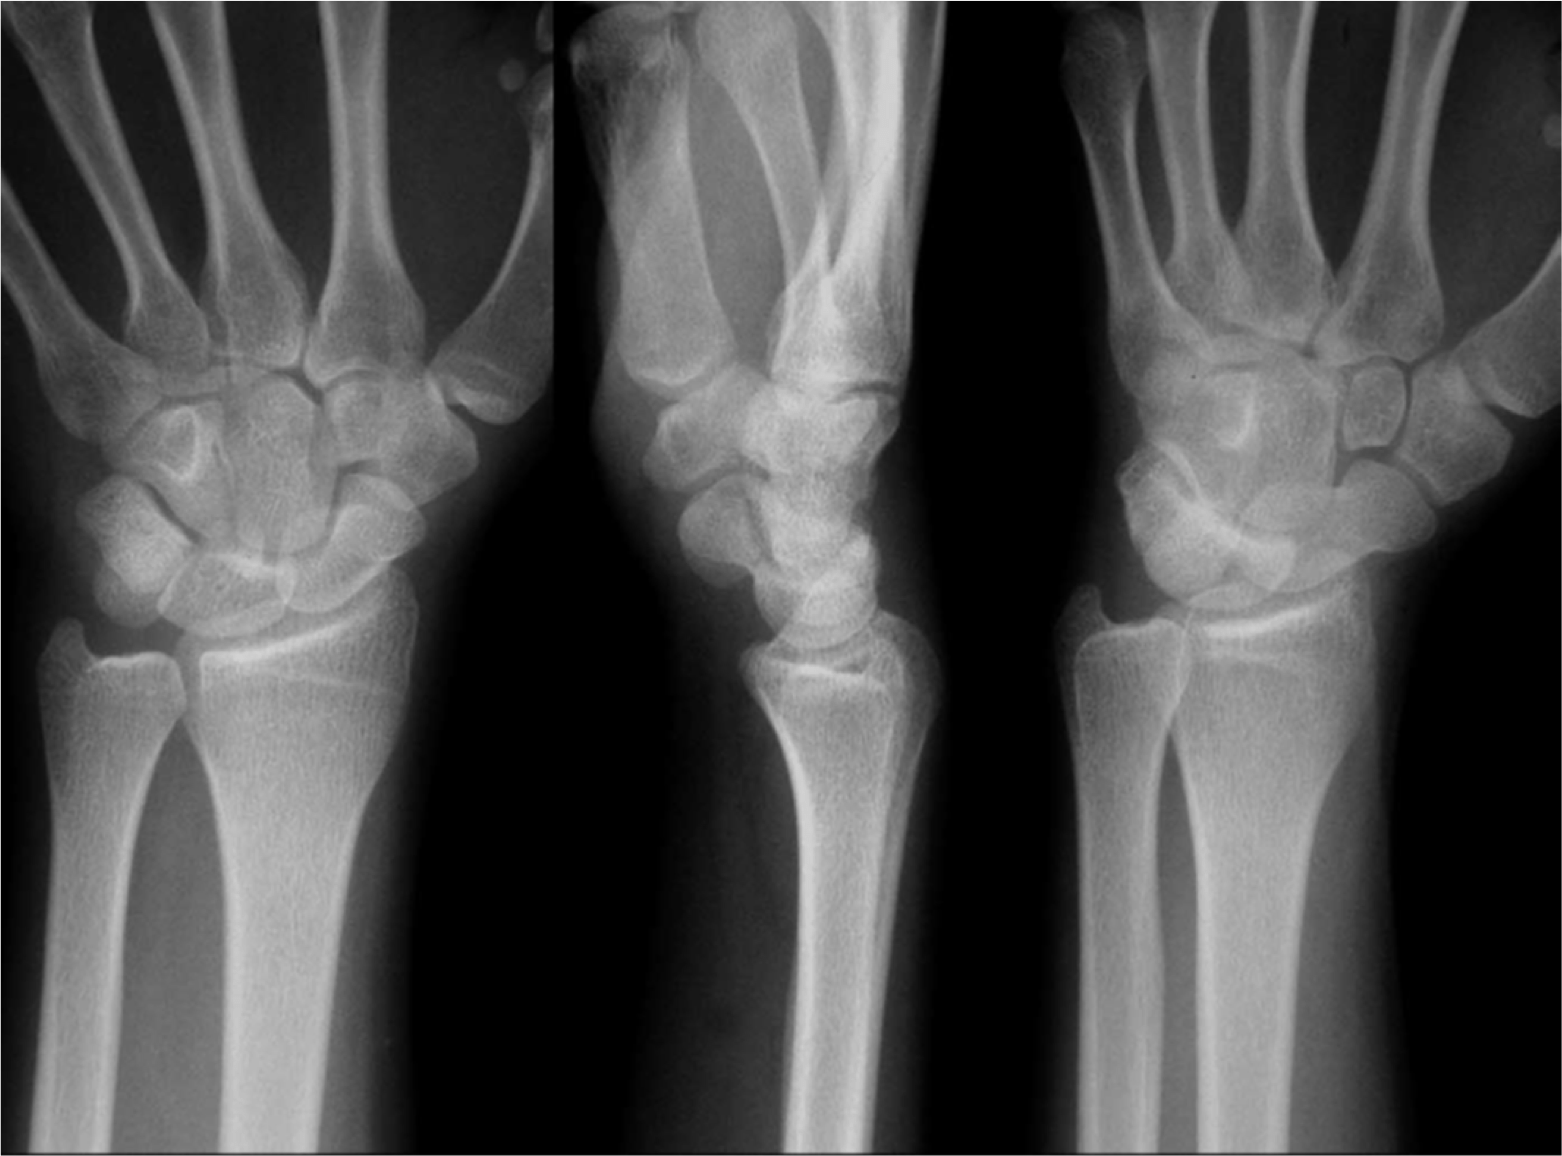

郭俊毅物理治療師表示檢查的方式有徒手檢查、X光及超聲波等來確定是哪個部位、哪種方式損傷。

檢查的方式有徒手檢查、X光及超聲波等來確定是哪個部位、哪種方式損傷。

舟狀骨骨折有時難以診斷,且如果不妥善處理容易造成骨骼遲愈或不愈合而發生骨骼缺血性壞死的情形。當診斷出確定為遠端橈骨骨折,其治療方式依嚴重程度分為手術及非手術治療,手術即使用內固定植入物讓骨頭愈合,而非手術治療則採用徒手復位加上石膏或副木固定,根據愈合程度來決定拆除石膏的日期。

舟狀骨骨折有時難以診斷,且如果不妥善處理容易造成骨骼遲愈或不愈合而發生骨骼缺血性壞死的情形。